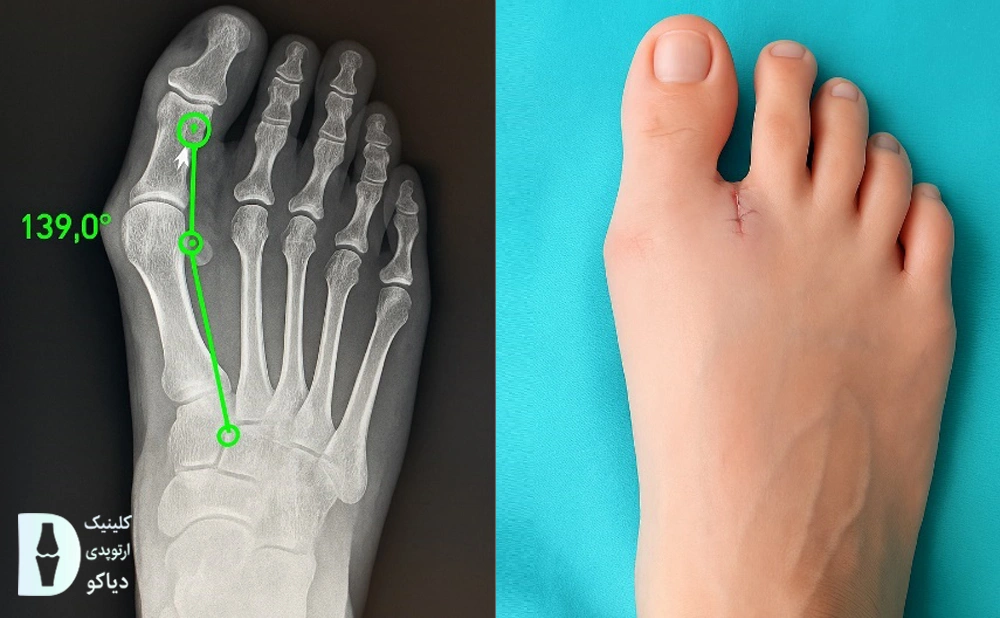

تشخیص شدت هالوکس والگوس توسط پزشک

پزشک ابتدا با معاینه فیزیکی، انحراف انگشت شست، میزان درد و محدودیت حرکت را ارزیابی میکند. برای بررسی دقیقتر شدت هالوکس والگوس، معمولاً عکس رادیولوژی (X-ray) از پا در حالت ایستاده گرفته میشود.

این تصویر به پزشک کمک میکند تا انحراف انگشت، وضعیت مفصل و سلامت استخوانها را بهتر بسنجد. در نهایت، شدت هالوکس والگوس معمولاً بر اساس دو زاویه HVA (زاویه هالوکس والگوس) و IMA (زاویه بین دو استخوان اصلی کف پا که زیر انگشت شست و انگشت دوم قرار دارند) تعیین میشود (منبع).